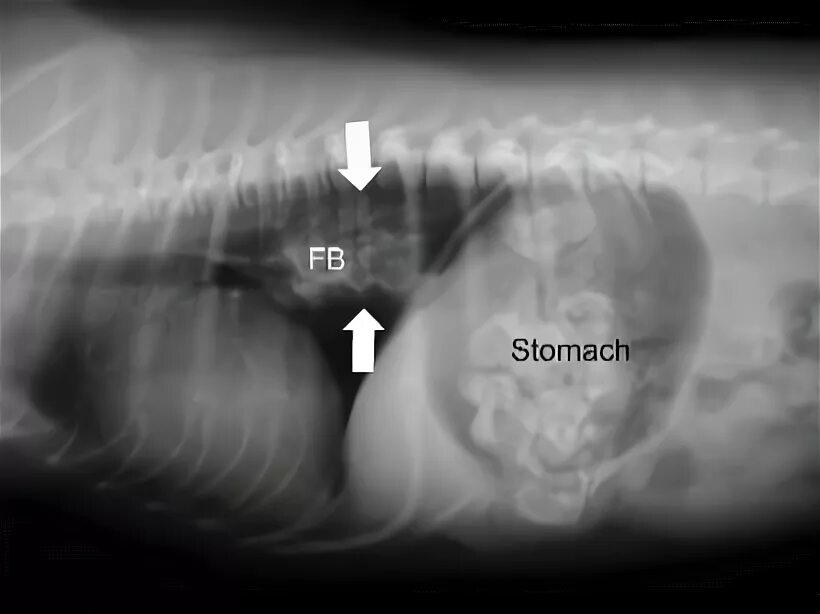

Как достать косточку из горла